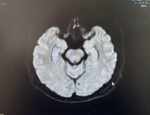

這樣的腎結(jié)石怎么手術(shù) 成年男性,雙腎重積水,左側(cè)已手術(shù)通暢,右側(cè)怎么選擇術(shù)式?